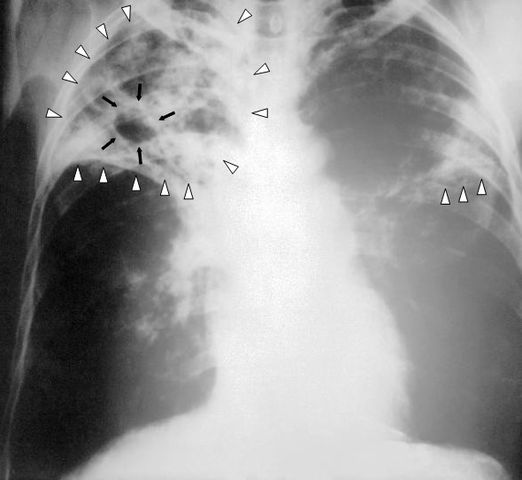

English: An anteroposterior X-ray of a patient diagnosed with advanced bilateral pulmonary tuberculosis. This AP X-ray of the chest reveals the presence of bilateral pulmonary infiltrate (white triangles), and „caving formation“ (black arrows) present in the right apical region.The diagnosis is far-advanced tuberculosis.

Deutsch: Eine Röntgenaufnahme im anterior-posterioren Strahlengang eines Patienten, bei dem eine beidseitige Lungentuberkulose festgestellt wurde. Diese Thorax-Aufnahme zeigt beidseitige Lungeninfiltrate (weiße Dreiecke) und eine sogenannte „Kaverne“ (schwarze Pfeile) im rechten Oberfeld. Sie entspricht der Diagnose einer fortgeschrittenen Lungentuberkulose.

Polski: Zdjęcie rentgenowskie w projekcji przednio-tylnej AP pacjenta ze zdiagnozowaną zaawansowaną, obustronną gruźlicą płuc. Na tym zdjęciu AP klatki piersiowej uwidoczniono obecność obustronnego zajęcia płatów (białe trójkąty) i "formowania jam" (czarne trójkąty) obecne w prawym szczycie płuca. Zdiagnozowano zaawansowną gruźlicę.

Español: Una placa anteriorposterior de rayos X de un paciente diagnosticado con avanzado tuberculosis en ambos pulmones. Esta radiografia del pecho revela la presencia de una infiltracion (triangulos blancos), y una cavidad (flechas negras) presente en el lado derecho. El diagnostico es Tuberculosis en un grado severo de avance.

Français : Radiographie thoracique d'un patient atteint d'une tuberculose a un stade avancé touchant les poumons de façon bilatérale. On décèle la présence de multiple micro-nodules bilatéraux a prédominance supérieure (triangles blancs) ainsi que la présence d'un caverne tuberculeux au niveau apical droit (flèches noires).

Русский: Рентгенограмма в передне-задней проекции пациента с двухсторонним туберкулёзом лёгких. На снимке выявляется двухстороннее ограниченное затемнение (инфильтрация легочной ткани, отмечена белыми треугольными стрелками) и полостное образование (формирующаяся каверна, отмечена чёрными стрелками) в верхем поле правого легкого. Диагноз: прогрессирующий туберкулёз.

Italiano: Radiogramma del torace in proiezione anteroposteriore in paziente con tubercolosi polmonare bilaterale avanzata. Presenza di infiltrati bilaterali (triangoli bianchi} e formazioni cavitarie (frecce nere) in apice polmonare destro. La diagnosi è tubercolosi in fase avanzata